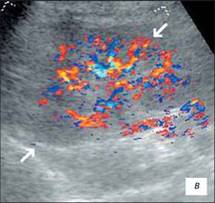

Ехограма гіпоплазії нирки

В-режимі(а),

В-режимі ЦДК (б, в).

Гемодинамічні показники артеріального кровотоку в нирковій артерії: Vps– 54 см/с, Ved– 22 см/с, RI– 0,4, PI– 0,7.

В-режимі (а)

В-режимі ЦДК (б).

На даному УЗД визначають зменшену в розмірах нирку з порушенням правильності її контурів, нирка насилу диференціюється від навколишніх тканин; різко порушена або відсутнє кортико-медуллярная диференціювання; візуалізуються дифузні нерівномірні зміни паренхіми нирки з гетерогенним підвищенням эхогенности; дилатація чашечно-мискової системи; виражене збіднення судинного малюнка ураженої нирки із зниженням швидкісних характеристик артеріального ренального кровотоку (10 – !!).